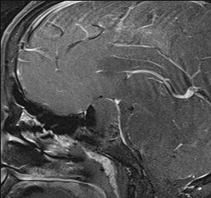

65 year old male with Pituitary Macroadenoma with cavernous sinus extension. Endoscopic Transsphenoidal Surgery done with Intraoperative MRI showing residual tumor in the cavernous sinus region under the left carotid artery. Post op MRI showing on the right no residual tumor in the sinus. (T1 contrast above and T2 coronal sections below).